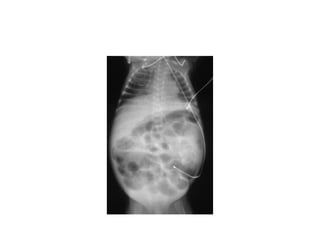

imaging

• Multiple gas filled loops of intestine

• Pneumatosis intestinalisc: pathognomonic for

NEC

• a collection of cystic or linear lucencies in the

bowel wall,

• Frequency may reach 19-98%but may be

absent in upto 14% of cases of NEC

imaging • Multiple gasfilled loops of intestine • Pneumatosis intestinalisc: pathognomonic for NEC • a collection of cystic or linear lucencies in the bowel wall, • Frequency may reach 19-98%but may be absent in upto 14% of cases of NEC

• 25.

• Portal venousgas: linear branching radiolucencies overlying the liver and often extending to its periphery • incidence of 10% to 30%.poor prognosis • Pneumoperitoneum: in 12-30% of patients • Best seen on lateral decubitus film • Football sign, double wall sign, • Only 63% of patients with perforation show the xray sign

• 26.

• Intraperitoneal fluid:gasless abdomen, flank opacity, separation of bowel loops • Persistent dilated bowel loop: dilated bowel loop remained unchanged for 24 to 36 hours